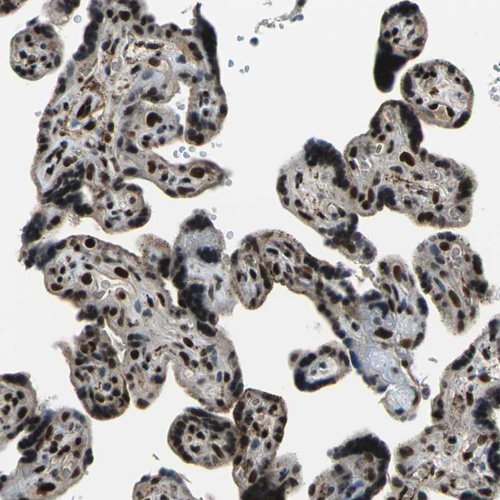

Immunohistochemical staining of human cerebral cortex, gastrointestinal, placenta and testis using Anti-ELF2 antibody HPA006057 (A) shows similar protein distribution across tissues to independent antibody HPA071166 (B).